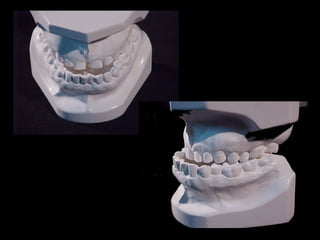

Modelos PreoperatoriosModelos Preoperatorios

Arcada Superior:

Forma oval

Paladar profundo

Totalidad de órganos dentarios a excepción de tercer molar izq.

Restauraciones deficientes

Arcada Inferior:

Forma ovalada

Colapso posterior

Ligero apiñamiento de anteriores

Rotación de premolares

Modelos vista lateral

prequirúrgica

Clase III molar y caninaClase III molar y canina